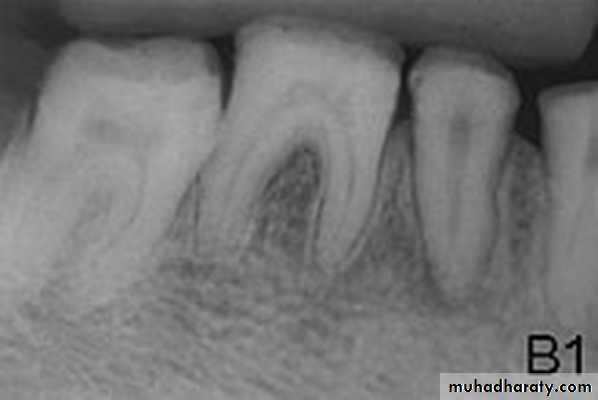

2. Fusion: two teeth fused with two pulps3. Gemination: wide crown with one pulp

Reasons

FusionFusion of two tooth germs during

Proliferation stage

Geminationan attempted division of a single tooth germ by invagination occurring during the